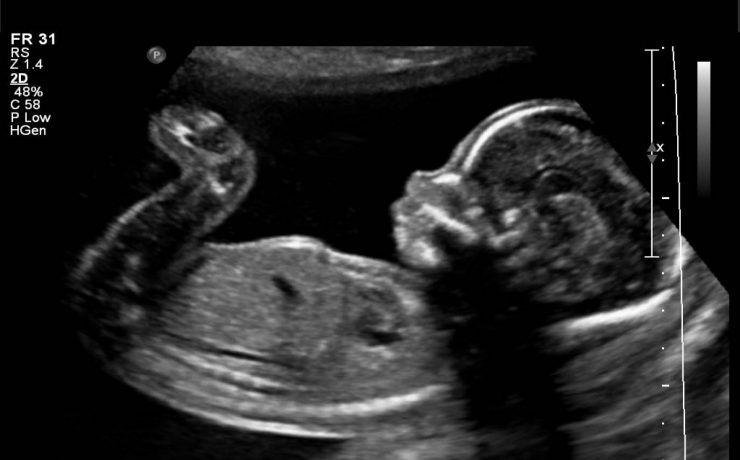

Se trata de femenina de 28 años de edad con antecedentes de leucemia senil y cáncer de páncreas; con diagnóstico histológico de neurofibroma. En abril de 2010 se detecto por USG una lesión en la apófisis unciforme y en la cabeza del páncreas de 2.3